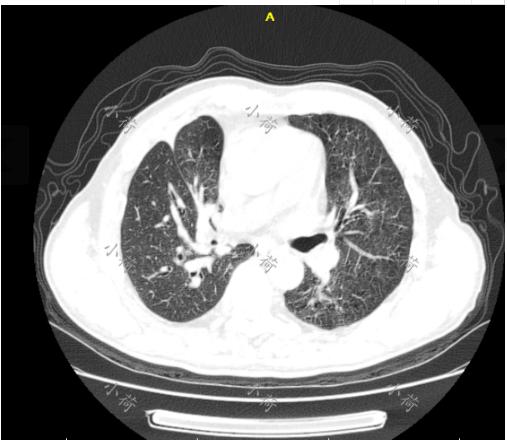

患者因咳嗽咳痰,痰中带血于2018-08-28日在人民医院门诊就诊查胸部CT:考虑右肺上叶癌伴周围阻塞性炎症,纵隔淋巴结肿大。

1.胸部CT:1、“肺癌术后化疗后”;2、右肺少许炎症;3、两肺纤维灶、局部钙化;4、纵隔小结节、主动脉及冠状动脉钙化。

1.右肺上叶后段一软组织团块影,其内可见小空洞影,放射性摄取异常增高;两肺多发斑点结节影,放射性摄取未见增高;纵隔上段血管前、气管前腔静脉后、隆突下及双肺门可见稍大淋巴结影,放射性摄取增高,考虑右肺上叶后段肺癌伴阻塞性炎症,伴双肺内及淋巴结转移可能大,建议经皮肺穿刺活检。